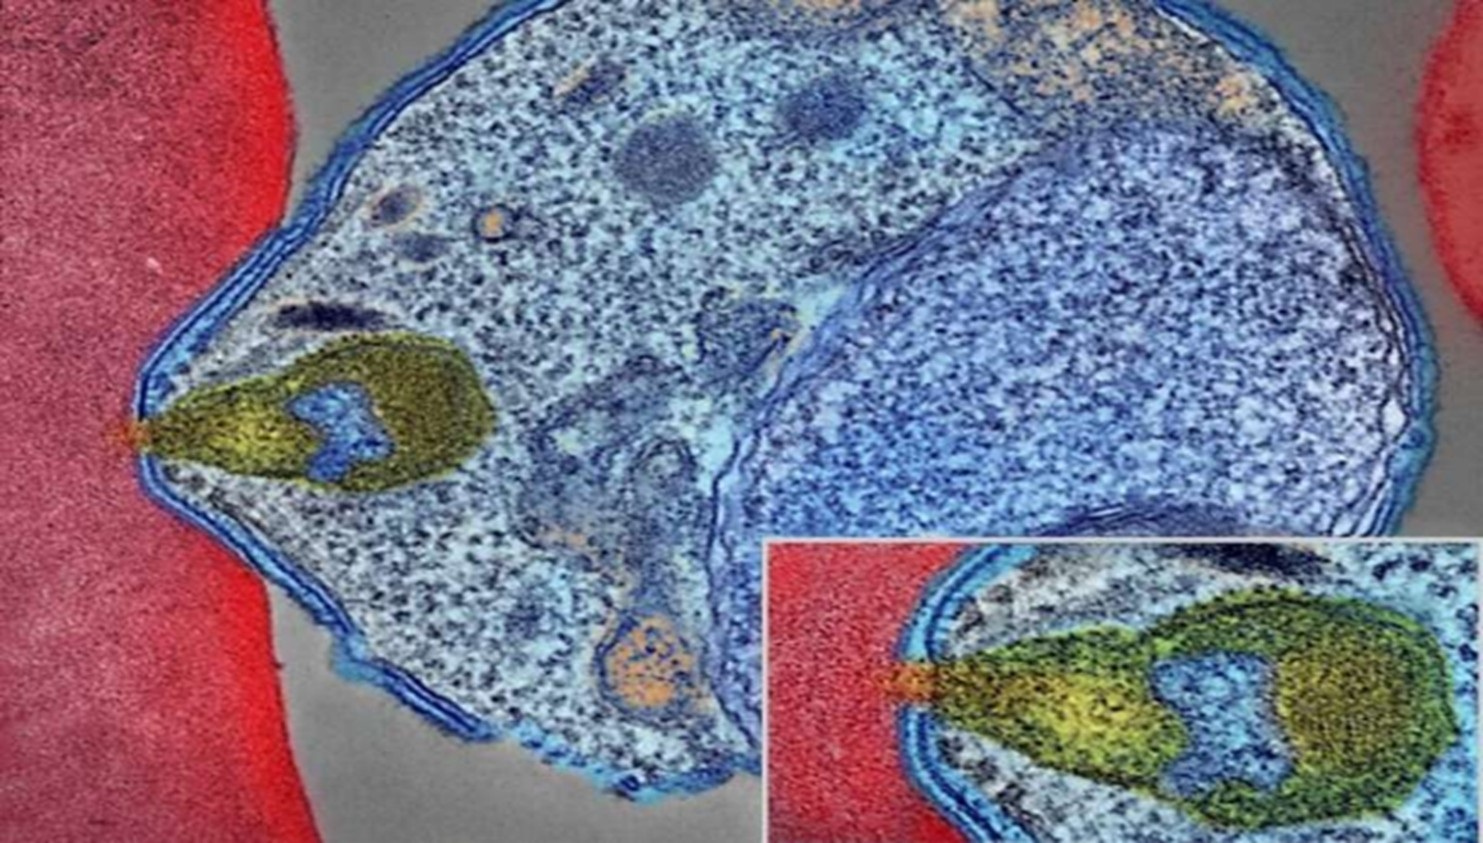

Bệnh sốt rét, do ký sinh trùng Plasmodium falciparum gây ra, vẫn là một mối đe dọa sức khỏe toàn cầu nghiêm trọng, cướp đi sinh mạng của 600.000 người mỗi năm, chủ yếu là trẻ nhỏ ở châu Phi cận Sahara. Khả năng miễn dịch với sốt rét thể nặng phát triển sau nhiều lần nhiễm bệnh và được điều hòa bởi kháng thể có chức năng ngăn chặn các protein bám dính PfEMP1 đa dạng cao của ký sinh trùng không cho chúng liên kết với thụ thể protein C nội mô người (EPCR) trên thành mạch máu.

Phân tích cấu trúc protein, được thực hiện cùng các nhà nghiên cứu tại Viện Nghiên cứu Scripps ở California, đã tiết lộ cách thức kháng thể trung hòa phổ rộng này liên kết với các phần còn lại được bảo tồn trên các biến thể PfEMP1 khác nhau để ngăn chặn sự bám dính của ký sinh trùng.